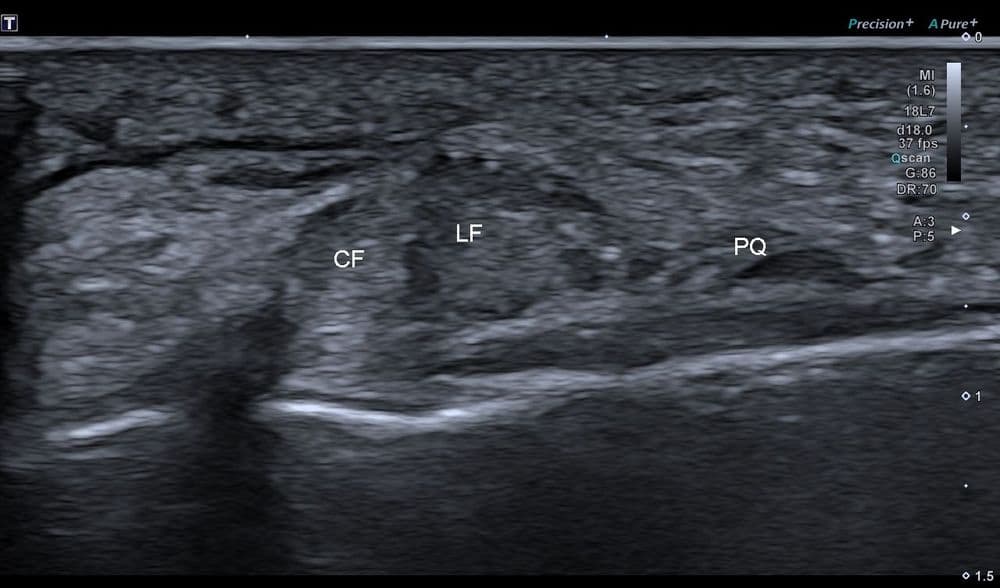

Douleur non traumatique latérale à la cheville, exacerbée par l'activité physique.

US